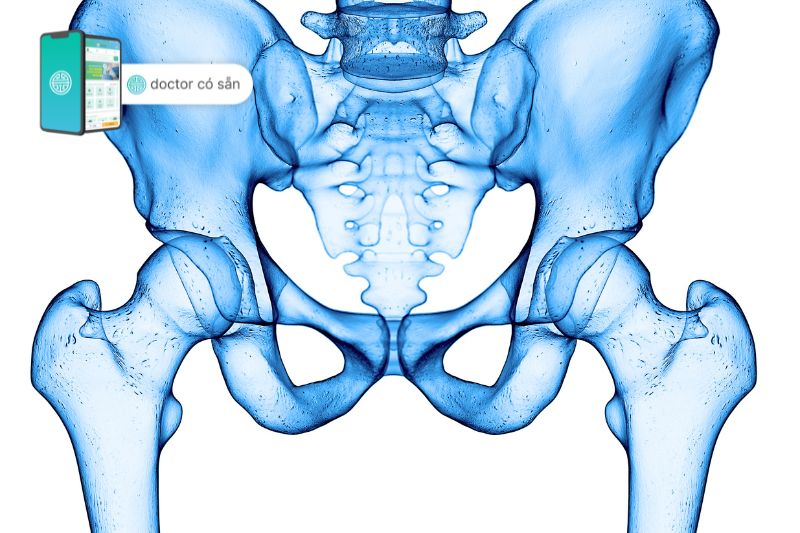

Tổng quan về khớp háng

Khớp háng là một trong những khớp lớn nhất cơ thể nằm giữa xương đùi và xương chậu, gồm 2 phần là chỏm xương đùi hình cầu và ổ cối của xương chậu lớn. Trên bề mặt 2 xương này là lớp mô trơn, hay còn được gọi là sụn khớp, giúp khớp cử động dễ dàng.

Khớp háng là bộ phận quan trọng hỗ trợ nâng đỡ trọng lượng của cơ thể và cần thiết cho các chuyển động bao gồm đi, đứng và vận động. Bất kỳ chấn thương hay bệnh lý nào liên quan đến khớp háng đều có thể gây đau và ảnh hưởng nghiêm trọng đến cuộc sống sinh hoạt hàng ngày.

Cấu tạo khớp háng nhân tạo bán phần

Có nhiều loại khớp háng nhân tạo bán phần với các loại chất liệu và kích cỡ khác nhau, nhưng cấu tạo chung có 2 phần:

- Phần chuôi xương đùi

Là phần đóng vào lòng tủy của xương đùi, thân chuôi có các khứa giúp tăng độ bám dính vào thân xương đùi, đỉnh chuôi có cổ gắn với phần chỏm nhân tạo.

- Phần chỏm xương đùi nhân tạo

Có chất liệu là kim loại hoặc gốm được lót một lớp polyetylen tạo bề mặt trơn, giảm hao mòn khi gắn với ổ cối tự nhiên của cơ thể.